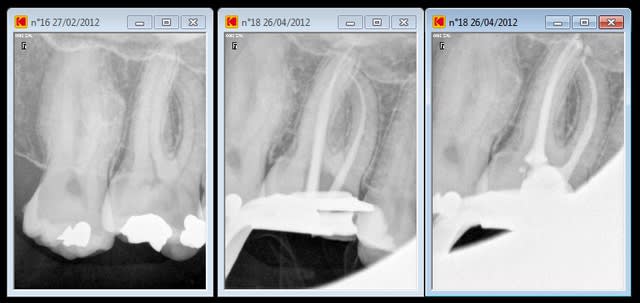

90 mn 2 molar endo + extrac 38. Un peu lent du à la difficulté à anesthésier (30 mn). les crochets apicaux traités comme si ils n'existaient pas avec le r25.